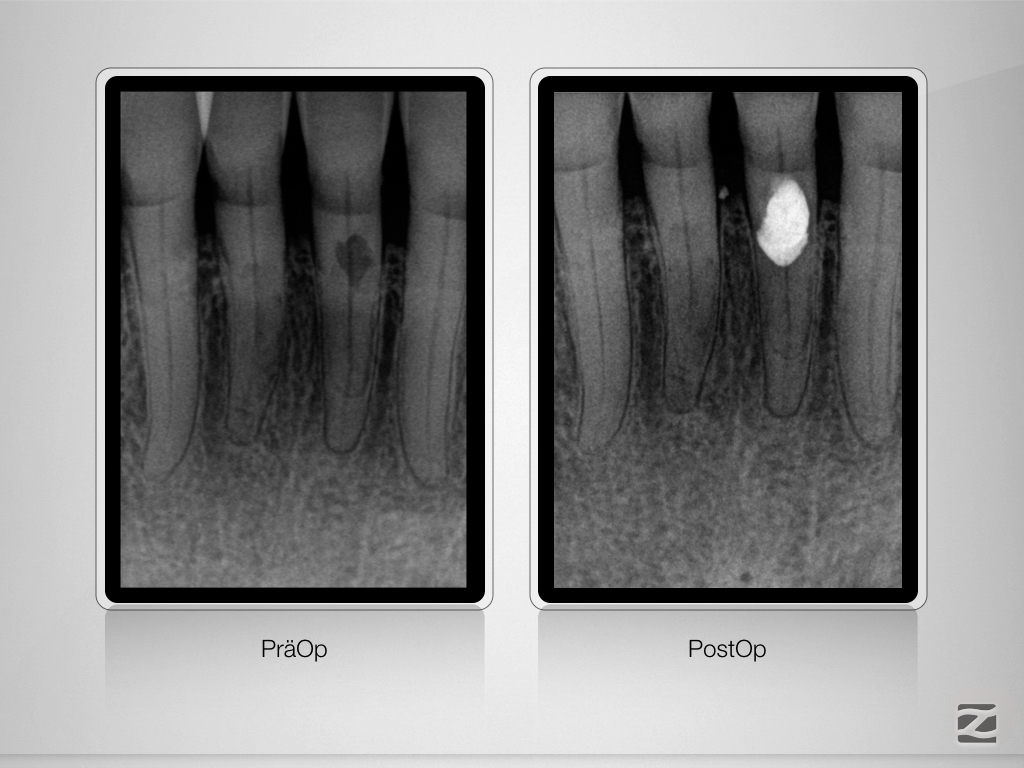

Trauma, externe Resorption & Pulpotomie